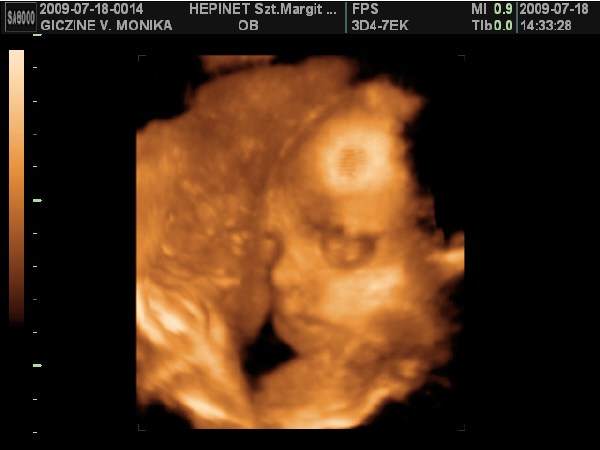

Lányok hoztam nektek képeket: :D :D

Kép

Ezek a képek szombaton készűltek. Bár nehéz volt jó képeket csinálni Lauráról, mert nagyon a méhlepény felé volt fordúlva. :D

Minden tökéletes vele, kb: 1 kilós már.

Ja!

És nagyon hasonlít a bátyjára. :lol: :lol: :lol: